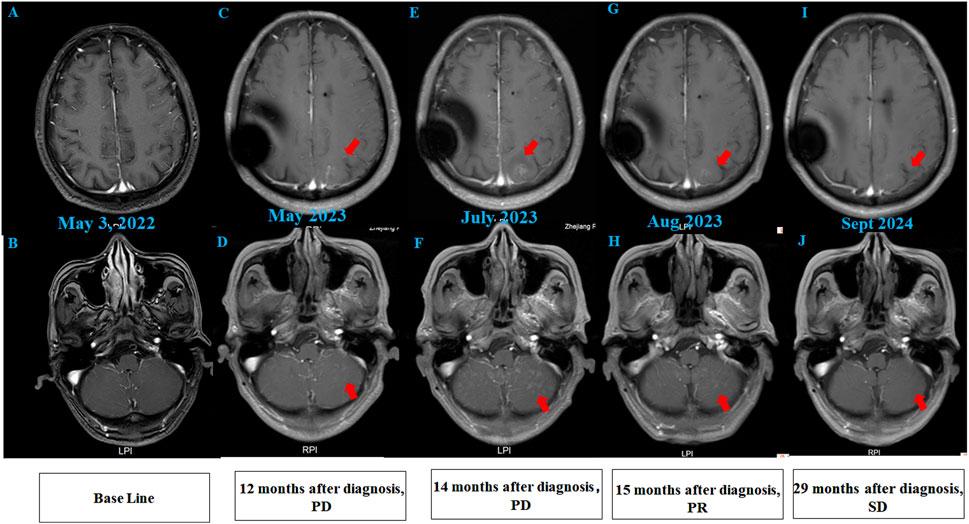

MRI scans showing axial views of the brain over time. Panels A and B from May 3, 2022 show baseline images. Panel C and D, 12 months after diagnosis, indicate progression with red arrows. Panels E and F, July 2023, show continued progression. Panels G and H, August 2023, reflect further changes. Panels I and J, September 2024, show stabilized disease, marked as

Figure 2. Brain MRI findings of the patient. (A,B) Initial brain MRI demonstrated T2/FLAIR hyperintensities in the white matter (Fazekas grade 1) and age-related cerebral atrophy. (C,D) MRI at 12 months post-diagnosis (after 12 cycles of intrathecal pemetrexed) revealed new abnormal signal foci in the left frontal lobe, bilateral parietal-occipital lobes, and cerebellum, indicating progressive disease (PD). (E,F) Post-whole brain radiotherapy, MRI showed increased abnormal signals compared to prior imaging. (G,H) After 2 cycles of intrathecal thiotepa, MRI demonstrated slight regression of metastatic tumors, consistent with partial response (PR). (I,J) Follow-up MRI revealed stable disease (SD), with no further progression of lesions.

After 6 months of maintenance treatment, the patient developed worsening neurological symptoms, including unsteady gait and dizziness. A head MRI revealed multiple abnormal signal foci (Figures 2C,D). Due to confirmed intracranial metastasis, the patient underwent whole brain radiotherapy (WBRT) (3000 cGy/10 fx), but neurological symptoms persisted. CSF cytology detected suspicious cells (Supplementary material online, Supplementary Figure S1), and follow-up MRI showed progression of intracranial lesions, particularly in the left frontal lobe (Figures 2E,F).

Given disease progression, the patient received intrathecal chemotherapy with thiotepa (10 mg) and dexamethasone (5 mg) on days 1, 8, and 15 of a 4-week cycle, alongside intravenous tislelizumab and bevacizumab on day 1. After two cycles, CSF cytology showed no abnormal cells, symptoms improved significantly, and the intracranial lesions slightly regressed (Figures 2G,H). Genetic testing of CSF confirmed a KRAS p.G12V mutation, consistent with the prior lung pathology.

To date, the patient has survived for 29 months since LM diagnosis, maintaining a performance status of 1 and a good quality of life with stable pulmonary and intracranial disease on imaging (Figures 1G,H; Figures 2I,J). The treatment summary of the patient is shown in Figure 3.